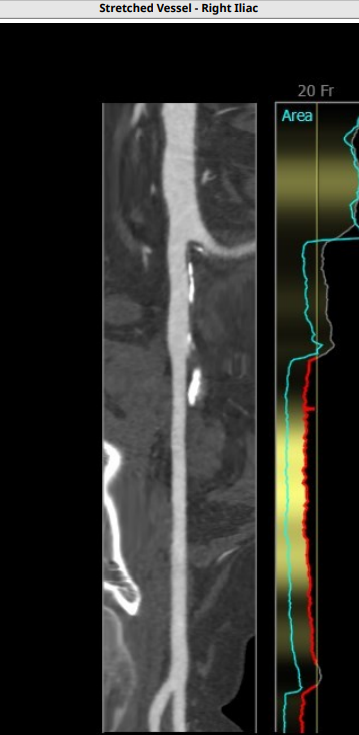

入路